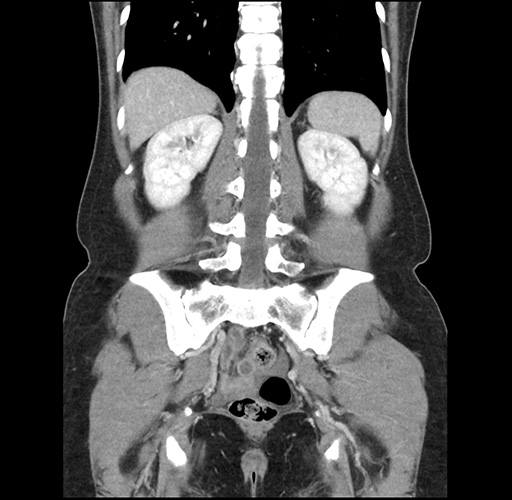

Imaging Analysis

Look through the patient's CT scan to identify any areas of concern for the necessary procedure.

Based on your CT findings, which issue(s) would give reason for "planned slowing down moment(s)" in this case?